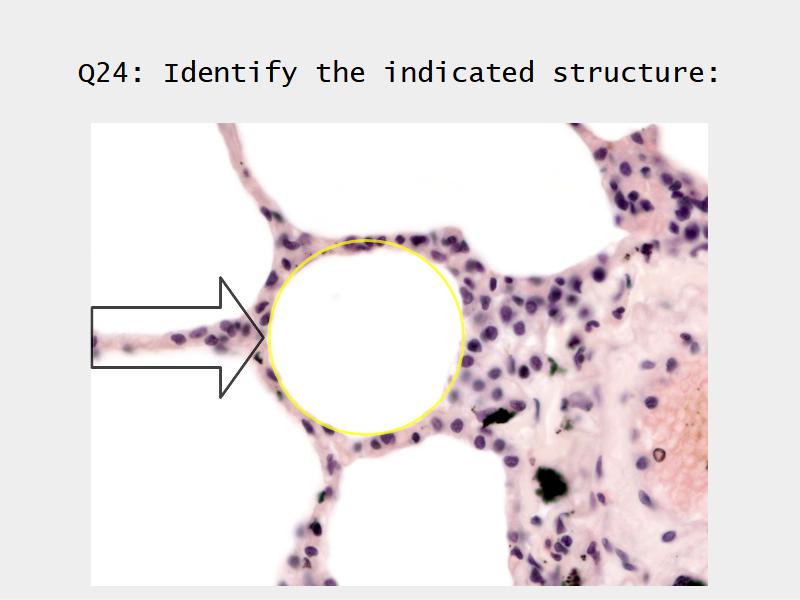

- Alveoli

Lungs